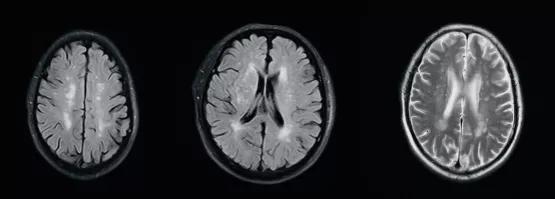

髓腔脱失的原因有很多,包括先天代谢性和后获得性。先天代谢性脱髓鞘主要指的是脑白质营养不良,以儿童青少年起病居多,这类疾病脱髓鞘在影像上多呈广泛对称性。后天性获得性脱髓鞘的病因又有很多种,包括缺血、炎症、感染、代谢、中毒、外伤等。更多见的是由高血压、糖尿病、高血脂等导致的微小血管病变引起缺血,继而导致髓鞘的脱失,也就是我们最常见的缺血性脱髓鞘,其本质是脑梗塞。这些脱髓鞘往往是个慢性的过程,一般没有临床症状,只有在做颅脑核磁检查时才被发现;病灶个头通常较小,数量上有时个别几个,有时候也可以有不少,呈点灶状或小片状分布在皮层下或者深部脑白质或者侧脑室前后角旁。看专科医生时,如果判断属于这种类型的脱髓鞘,就需要对上述相关的危险因素进行筛查、监测和管理,并完善颈部血管超声、经颅多普勒、颅内血管核磁等检查,看看大中血管的情况,如果没有比较大的斑块,没有明确的血管狭窄。就要管理危险因素(血压、血糖、血脂、吸烟过量饮酒等)并每半年到一年复查一下就行了。

(FLAIR序列及T2WI序列显示缺血性脱髓鞘病变)

还有一部分人有上述特点病灶,但是没有筛查到上述危险因素,往往给大家带来困扰,到底是啥原因导致的呢?其实在我们小时候都会多次接种疫苗甚至长大还会接种或加强一些疫苗,如狂犬疫苗、乙肝疫苗,有的冬天还会接种流感疫苗;还有就是类似感冒的病毒感染,从小到大估计每个人都会经历无数次。实际上接种疫苗或者感冒后脑子里就可能出现几个甚至多个病灶,从本质上讲它们是炎性脱髓鞘病灶,只是人体轻的、限制性的一个免疫反应和结果。这种脱髓鞘病灶也绝大多数是幼时留下来的,被后来体检或者其他原因做颅脑核磁时所发现。如看专科医生,判断属于此种情况,就不必担心了。因为这些病灶一是无症状性的,二是这些病灶长期稳定存在,如果是第一次做核磁发现,那么第二、三年再复查比较一下,如果较前没有增多和变化,就基本不需要管它们了。这里提醒大家不要过于纠结,希望这些病灶能够消失,因为它们是陈旧性病变,不会消失而会稳定一直存在;但是它们既没有症状,未来也不会变成活动性病灶,所以请大家不要担心。

(常见无症状炎性脱髓鞘病变)